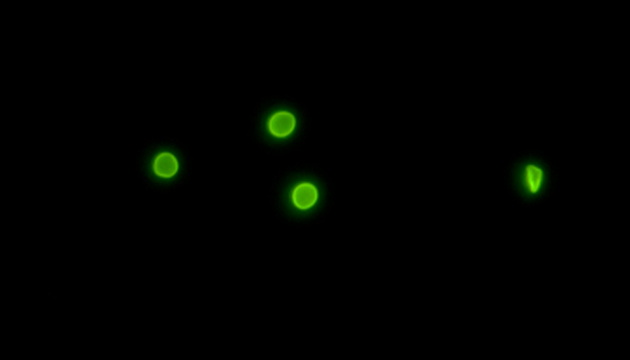

两虫指的是贾第鞭毛虫(Giardia)和隐孢子虫(Cryptosporidium),它们是主要的水源性原生动物寄生虫,通过被污染的饮用水或食物感染人类,引起腹泻等疾病,且大多数抗生素对其无效,严重威胁水质安全和人类健康。

显微成像在检测两虫中扮演关键角色,通过免疫荧光法结合专业的荧光显微镜,能高效区分并识别水体中的贾第鞭毛虫和隐孢子虫,确保饮用水安全。这种方法提高了检测的准确性和效率。